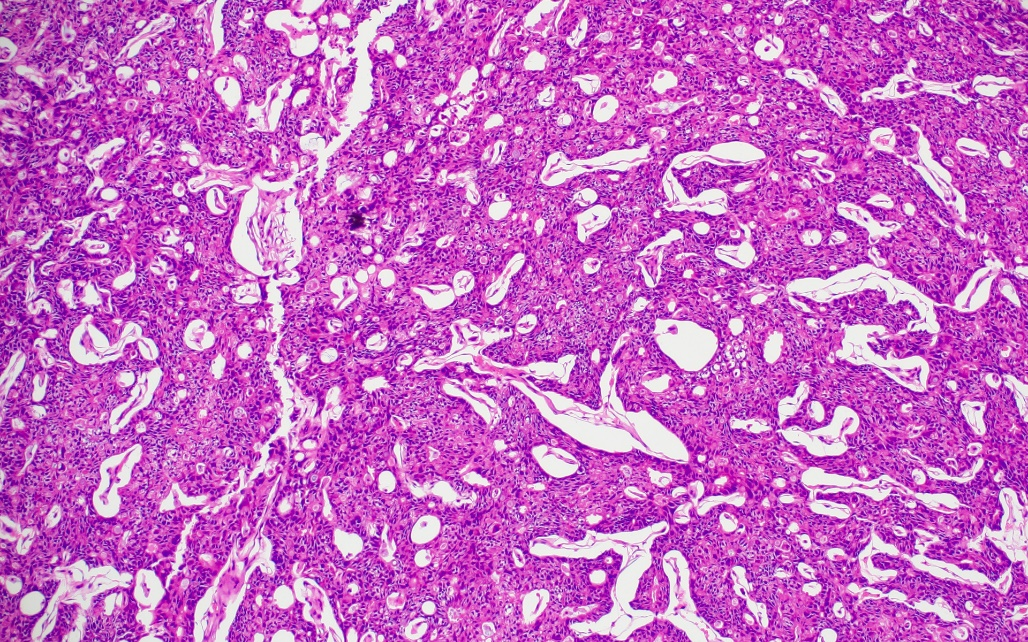

病理:符合胃癌病理特征

圖片5.png

圖片6.png